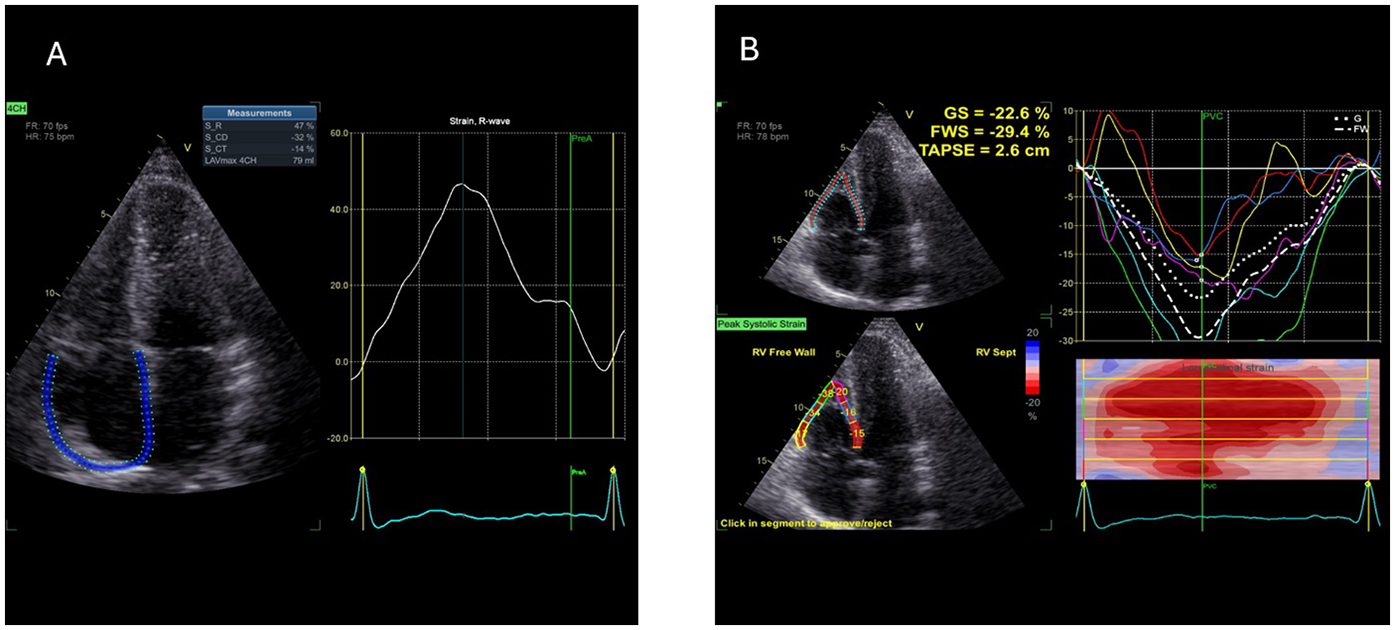

For RAS analysis, as there was no dedicated software at the time of the study period available, a left-atrial strain dedicated commercially available software (AFI LA GE Medical Systems, Milwaukee, WI, USA) was used (off-label). Right atrial border was semi-automatically traced by the examiner: right atrial free wall was traced as septal and septal wall was traced as left atrial free wall (Figure 1), contours of right atria were than adjusted manually by the performing examiner, and then RAS was automatically assessed by the software. As mentioned, R-RAS, CD-RAS and CT-RAS were analysed.

Figure 1

Example of 2D speckle tracking examination of right atrial (A) and right ventricular (B) strain—picture taken from control sample (2D ST, 2-dimentional speckle tracking; CD, conduit; CT, contraction; GS, global strain; FWS, free wall strain, R, reservoir; TAPSE, tricuspid anulus plane excursion).